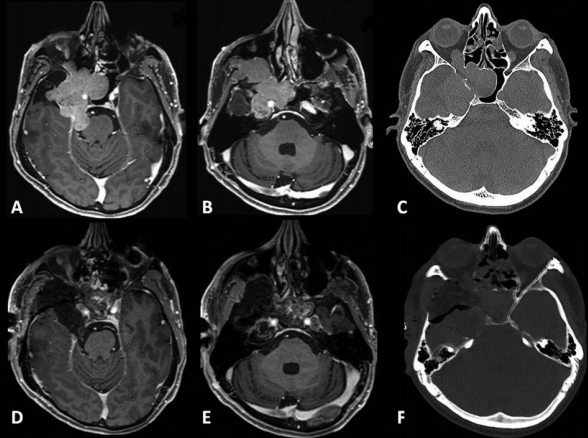

术前术后影像对比:(A)术前MRI显示脑膜瘤延伸至后颅窝(PF)、海绵窦(CS)、眼眶和蝶窦(SS)。(B)肿瘤延伸至中窝、翼腭窝(PPF)和颞下窝(ITF)。(C)术前CT显示更大的蝶翼侵蚀和SS受累。(D, E)术后MRI显示肿瘤完全切除。(F)术后轴位CT扫描显示用于闭合的脂肪移植物。

采用原额颞入路,显微镜+神经内镜-“双镜联合”,术后MRI显示肿瘤全切除。

53岁男性患者,7年前在外院手术切除2级脑膜瘤。因出现三叉神经V1、V2区麻木,V3感觉迟钝入院。MRI见巨大脑膜瘤复发侵犯右侧海绵窦、眶顶、SphS、PPF和ITF并通过Meckel’s腔(MC)延伸至小脑桥脑角(CPA)(图 a-c)。